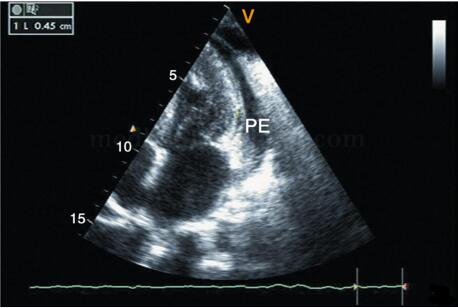

2﹒二维超声心动图 提示缩窄性心包炎的征象包括心包不同程度增厚,回声增强,尤以房室瓣环处为著,见图2‐1‐232;部分患者的心包可出现钙化,见图2‐1‐233,钙化的心包后方可出现明显的声影;四腔心切面可显示双心房增大、双心室相对较小,见图2‐1‐232;剑下四腔心切面可显示心包膜增厚、回声增强的程度,心室收缩及舒张受限;大动脉短轴及左心室长轴切面均可显示左心房增大。部分患者可出现不同程度心包积液(图2‐1‐234),心包腔内可见絮状物回声。由于心房压力增高,上下腔静脉、肝静脉扩张,且扩张的下腔静脉、肝静脉内径随呼吸变化不明显。

图2‐1‐234 缩窄性心包炎合并心包积液(PE),左室侧壁脏层心包增厚